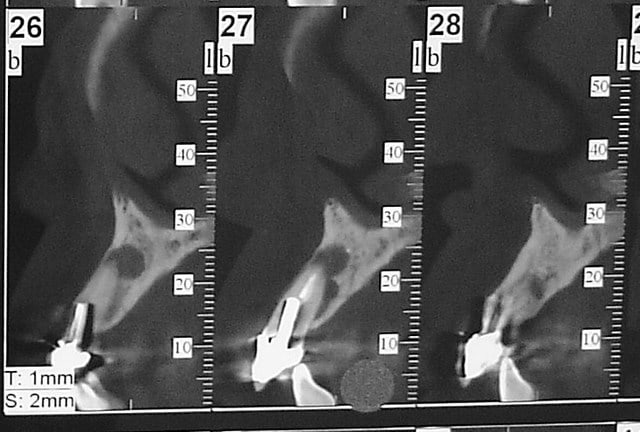

pluton

22/10/2011 à 11h59

le hasard fait parfois bien les choses...patient revu ce matin pour une "bricole" sur une restauration postérieure...

il est intéressant de voir la maturation des tissus mous...et en plus VS des différences au niveau de l'hygiène, pas mal secteur 2 mais perfectible secteur 1...

ici on est à 3 mois post pose prothèses d'usage...la photo, prise un peu décalée, donne l'impression d'une différence de hauteur des collets, mais il n'en est rien (ou alors très peu...)

quand même content du résultat...;-) même si j'ai (lourdement)insisté pour que l'hygiène soit un peu mieux suivie...